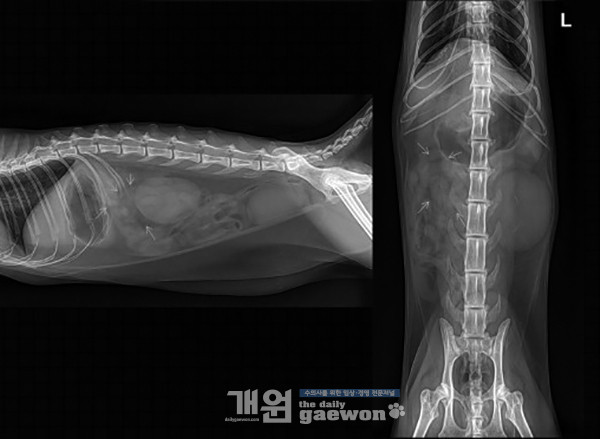

두번째 증례입니다. Abdomen에서 좌측 신장 음영의 위치로 8.7mm, 5.7mm 정도 크기의 curved linear shape으로 mineral opacity 음영이 관찰됩니다.

좌측 신장 음영의 크기는 L2 길이의 3배 정도로 크게 관찰되며, 좌측 신장 주변 peritoneal contrast가 다소 감소되어 관찰됩니다. Lateral view에서 방광 음영 caudal, slightly dorsal 측면으로 2.6mm 정도 크기의 mineral opacity 음영이 관찰됩니다.

우측 신장 음영의 margin은 뚜렷하게 관찰되지 않으나, L2 길이의 약 1.9배 정도로 작게 관찰됩니다. 위 및 장 분절의 특이적인 확장은 관찰되지 않습니다. 포함된 근골격계의 특이적인 소견은 관찰되지 않습니다.

감별진단으로서; (1)Enlarged Lt. kidney: acute renal injury, hydronephrosis, compensatory hyperplasia, neoplasia; (2)Small sized Rt. kidney: CKD; (3)Mineral opacity adjacent to UB silhouette: ureteral calculi, UB calculi; (4)Mildly decreased peritoneal contrast adjacent to Lt. kidney(retroperitoneal space): focal peritonitis, mild peritoneal effusion; (5)Esophageal dilation: dyspnea가 고려됩니다.